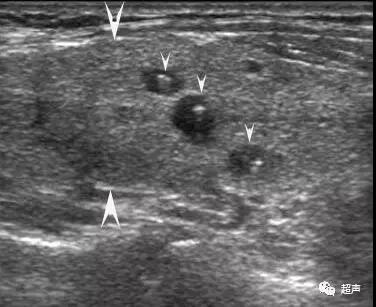

大箭头指向腺体,小箭头指向结节,结节外腺体回声不均

大箭头指向腺体,小箭头指向结节,有的结节伴弧形钙化,结节外腺体回声不均。